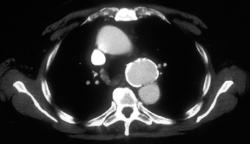

Teratoma Invades SVC